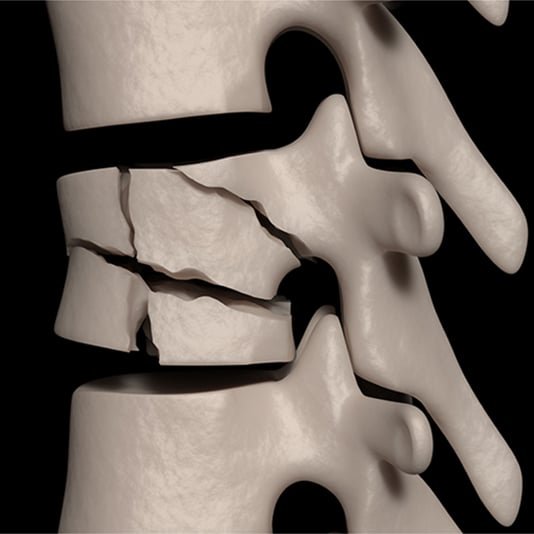

Osteoporosis and Vertebral Compression

Older patients and those with osteoporosis have a high risk of spinal fractures, particularly vertebral compression fractures. The main reason being low bone mass and strength, as well as an increased risk of falling. In these patients, vertebral compression fractures can occur during simple activities of daily living, such as coughing, sitting down quickly, or taking a step wrong.

As with many osteoporotic fractures, compression fractures are more common in women than men; however, the consequences are severe in both. Patients may experience acute and chronic pain, kyphotic deformity (increased forward curve of the spine), decreased quality of life, increased anxiety, depression, and death. Our geriatric doctors and nurses are involved in their care.